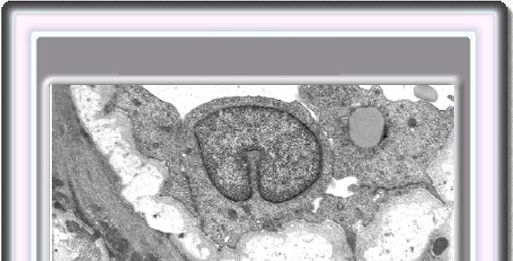

La biopsia de piel de los pacientes con CADASIL muestra en las microfotografías electrónicas una deformación de las células musculares lisas con infiltraciones de un material granuloso osmiofílico (GOM) lo que tiene un valor diagnóstico significativo